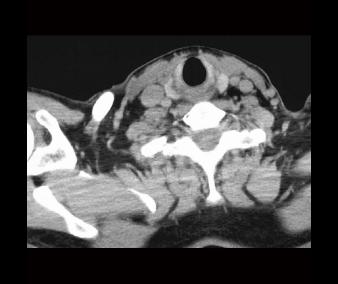

RadLab4CT02 RadLab4CT01

Labels off SCM m

carotid a scalene mm carotid a

strap mm

cricoid cart

SCM m esophagus thyroid gland

int jugular v vagus n

vertebral a

int jugular v thyroid longus colli

longus colli

scalene mm

vagus n

Normal CT review: Slices 9 & 10